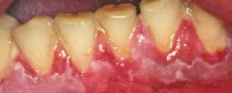

• PMN 功能不足 → 嚴重牙周病

• 快速的骨流失 → floating in air

• 瀰漫出血與增生性牙齦炎